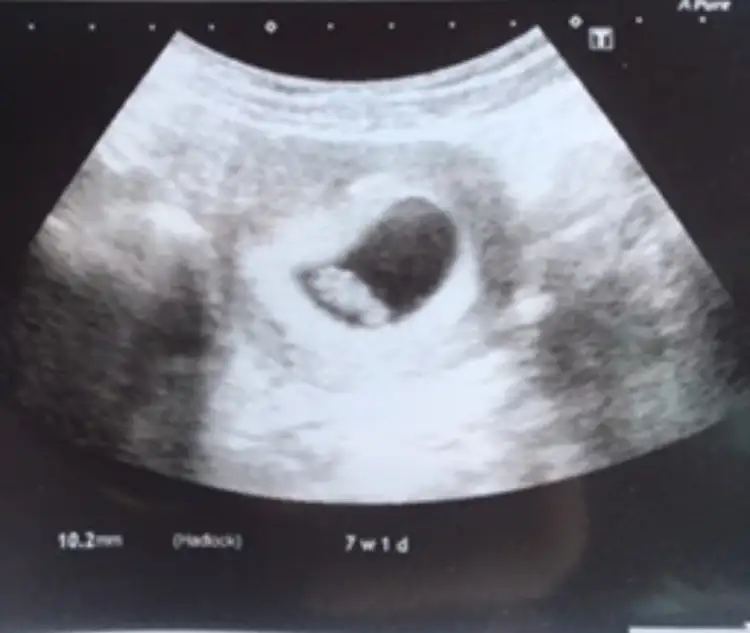

6-7 . haftalara ait ultrason görüntünüz eliniz de varsa inceleyin. Bebek sağ tarafta ya da sağ tarafa daha yakınsa kız , Eğer bebek sol tarafta ya da sol tarafa yakınsa cinsiyeti erkektir.